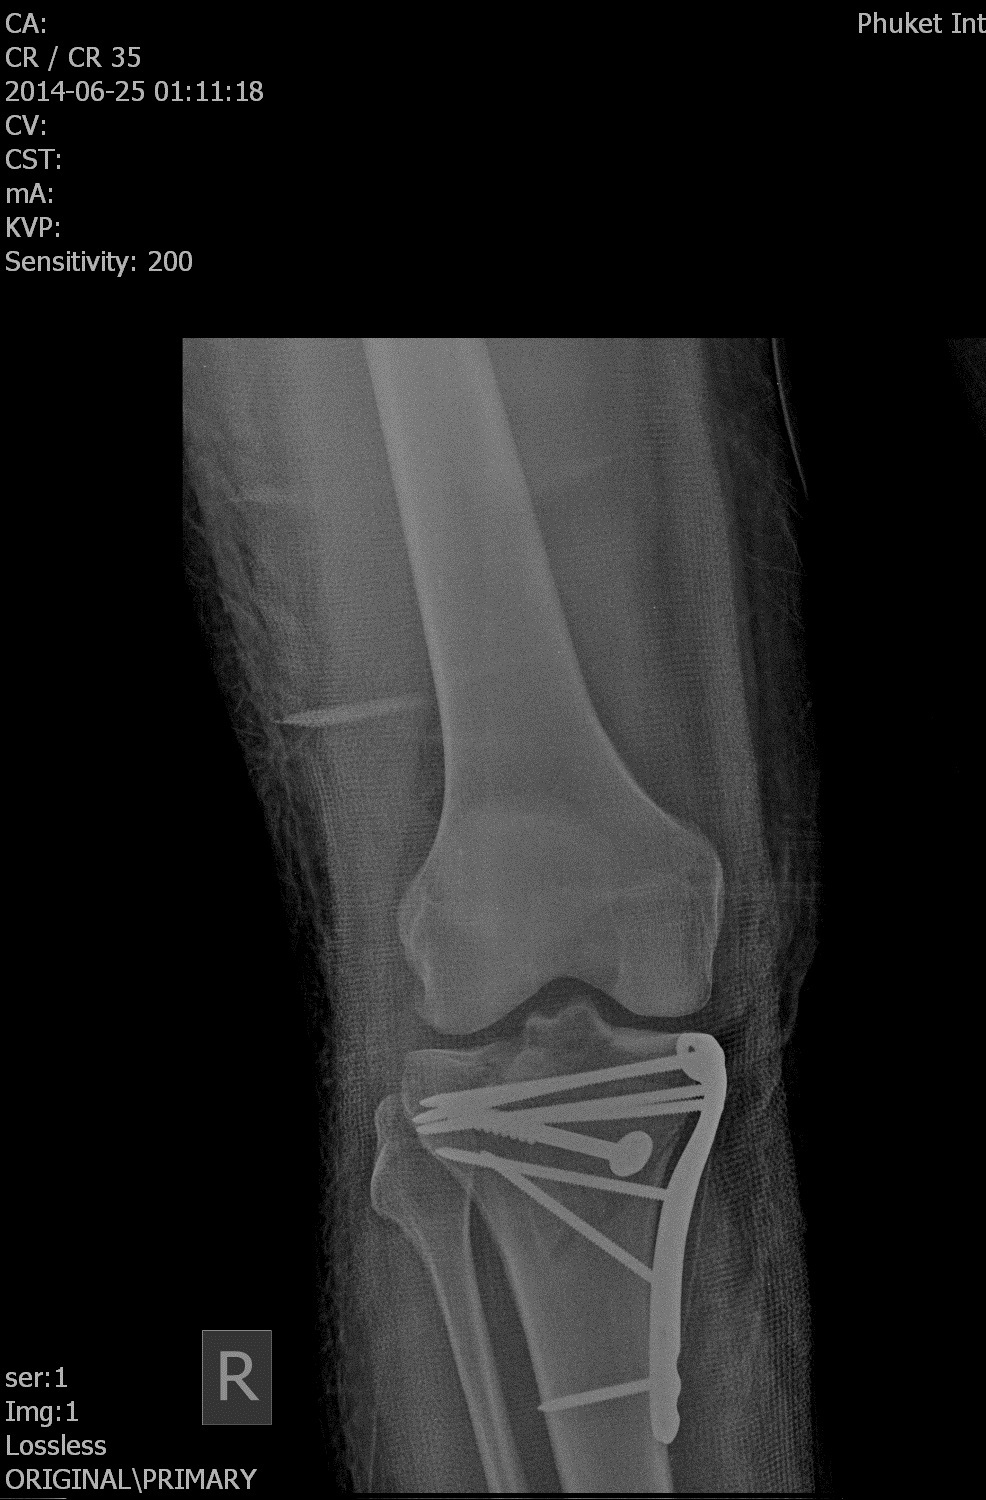

8 fantascop 7 лет назад Было-стало В Таиланде крепко шарахнуло волной об скалу. Раздробленное колено собрали саморезами. Вернулся с палочкой. Через год - только напоминание в виде шрама. [моё] Травма Операция Хирургия Не жесть Длиннопост